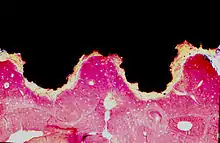

An osseointegrated implant is a type of implant defined as "an endosteal implant containing pores into which osteoblasts and supporting connective tissue can migrate".[2] Applied to oral implantology, this refers to bone grown right up to the implant surface without interposed soft tissue layer. No scar tissue, cartilage or ligament fibers are present between the bone and implant surface. The direct contact of bone and implant surface can be verified microscopically.

Osseointegration is a dynamic process in which characteristics of the implant (i.e. macrogeometry, surface properties, etc.) play a role in modulating molecular and cellular behavior.[14] While osseointegration has been observed using different materials, it is most often used to describe the reaction of bone tissues to titanium, or titanium coated with calcium phosphate derivatives.[15] It was previously thought that titanium implants were retained in bone through the action of mechanical stabilization or interfacial bonding. Alternatively, calcium phosphate coated implants were thought to be stabilized via chemical bonding. It is now known that both calcium phosphate coated implants and titanium implants are stabilized chemically with bone, either through direct contact between calcium and titanium atoms, or by the bonding to a cement line-like layer at the implant/bone interface.[16][17] While there are some differences (e.g. like the lack of chondrogenic progenitors), osseointegration occurs through the same mechanisms as bone fracture healing.[18][19]

For osseointegrated dental implants, metallic, ceramic, and polymeric materials have been used,[2] in particular titanium.[20] To be termed osseointegration the connection between the bone and the implant need not be 100%, and the essence of osseointegration derives more from the stability of the fixation than the degree of contact in histologic terms. In short it is a process where clinically asymptomatic rigid fixation of alloplastic materials is achieved, and maintained, in bone during functional loading.[21] Implant healing time and initial stability are a function of implant characteristics. For example, implants using a screw-root form design achieve high initial mechanical stability through the action of their screws against bone. Following placement of the implant, healing typically takes several weeks or months before the implant is fully integrated into the bone.[22][23][24] First evidence of integration occurs after a few weeks, while more robust connection is progressively effected over the next months or years.[25] Implants that have a screw-root form design result in bone resorption followed by interfacial bone remodeling and growth around the implant.[26]

Implants using a plateau-root form design (or screw-root form implants with a wide enough gap between the pitch of the screws) undergo a different mode of peri-implant ossification. Unlike the aforementioned screw-root form implants, plateau-root form implants exhibit de novo bone formation on the implant surface.[27] The type of bone healing exhibited by plateau-root form implants is known as intramembranous-like healing.[26]